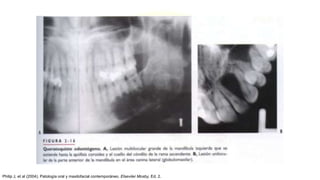

QUERATOQUISTE ODONTOGENO

• Quiste derivado de los restos (residuos) de la lamina dental,

con un compartimento biológico similar al de una neoplasia

benigna

• Zona del tercer molar y rama ascendente

• 2°-3° década

• Asintomáticos hasta que se infectan

RADIOLOGIA:

• Tendra el aspecto de una lesión solitaria bien definida o de

una radiotransparencia multilocular/poliquistica que

muestra un borde cortical delgado.